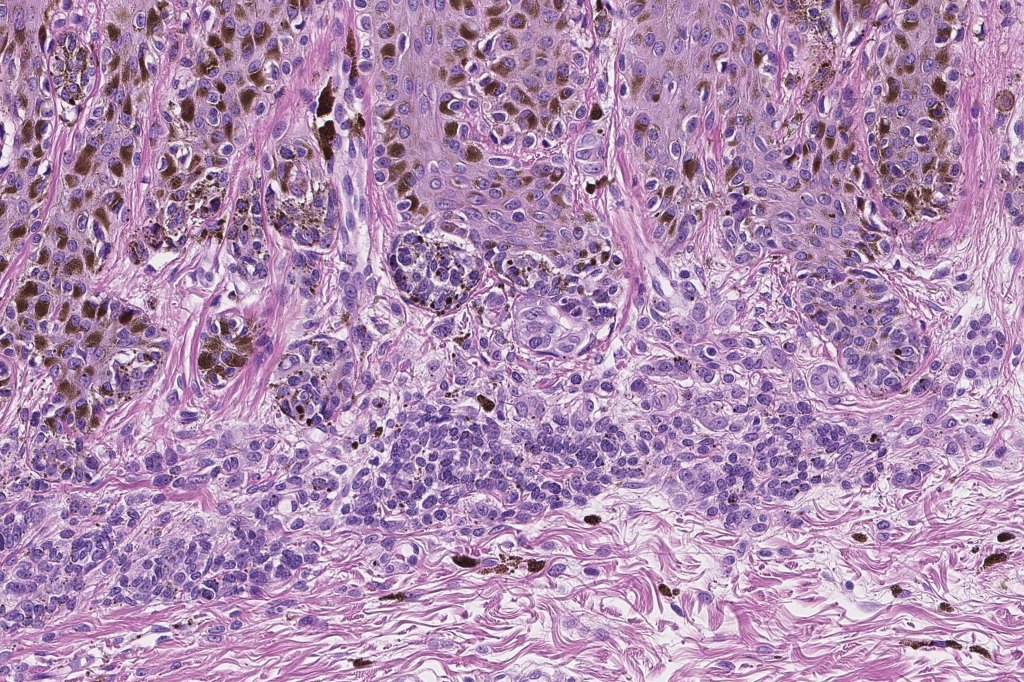

•Architectural disorder- lentiginous and nested, nests abnormally located (at the sides of the rete ridges & overlying the dermal papillae in addition to the tips of the rete ridges rather than solely occupying the tips of the rete ridges as is seen in banal nevi), horizontal orientation & bridging between junctional nests (this should not be confused with bridging between adjacent rete ridge squamous epithelium)

•Abnormal fine pigmentation (dusty)

•Cytological atypia- mild, moderate & severe (or more recently, low & high grade (WHO). The problem with the new WHO classification is that mildly dysplastic nevi are now included with the banal nevus category and moderate is low grade and severe is high grade. In all likelyhood, most pathologists will include mild & moderate atypia in the low grade category.

•Host response- eosinophilic & lamellar fibroplasia, increased vascularity, lymphocytic infiltration & pigment incontinence

•In compound lesions, the nest size should be smaller than the junctional ones and the degree of atypia the same or less

Dysplastic nevus in the majority of cases is instantly recognizable, often at low power. The most important differential diagnosis is obviously melanoma. In junctional lesions, widespread/uniform high grade atypia, frequent mitoses and Pagetoid spread are indicative of in situ melanoma. In compound lesions, dermal nests larger than junctional ones, expansile dermal nests, severe atypia and mitotic activity indicate the presence of melanoma